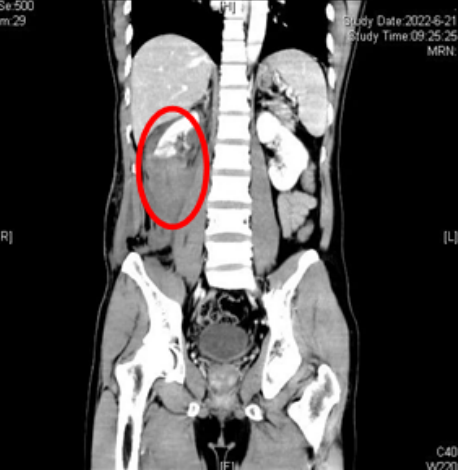

CT示患者右侧肾脏断裂、肾上极多处皮质裂伤,肾盂破裂,右肾周、腹腔及腹膜后多发积血